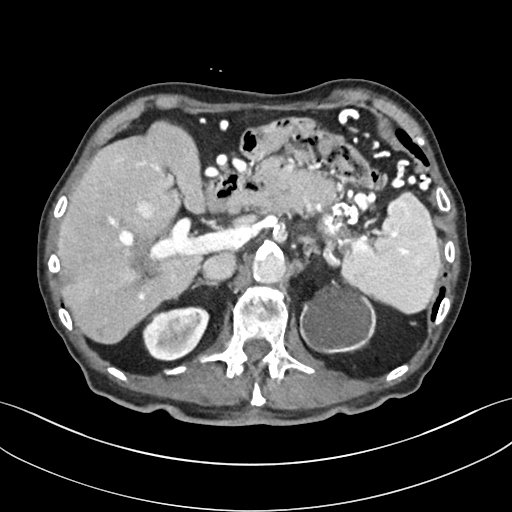

To demonstrate the effectiveness of the proposed network, we perform the qualitative comparisons over three representative abdominal images presented in Figs. 3, 5 and 7. For better evaluations of the image quality with different denoising models, zoomed regions-of-interest (ROIs) are marked by red rectangles and shown in Figs. 4, 6 and 8 respectively. Note that all results from different denoising models focus on two aspects: content restoration and noise-reduction. All CT images in axial view are displayed in the angiography window [-160, 240]HU.

The real NDCT images and corresponding LDCT images are presented in Figs. 3a and 3b. As observed, there are distinctions between ground truth (NDCT) images and LDCT images. Figs. 3a and 7a show the lesions/metastasis. Fig. 5a presents focal fatty sparing/focal fat. In Figs. 4a, 6a and 8a, these lesions can be clearly observed in NDCT images; in contrast, from Figs. 4b, 6b, and 8b, it can be seen that the original LDCT image is noisy, and lacks structural features for task-based clinical diagnosis. All adopted denoising models suppress noise to some extent.

To study the robustness of the adversarial learning framework in SMGAN-3D, we compared SMGAN-3D with the CNN-based methods, including CNN-L2, CNN-L1, RED-CNN [35], SL-net and MSL-net. It is worth noting that CNN-L2, CNN-L1, and RED-CNN are mean-based denoising methods, and SL-net and MSL-net are SL-based denoising methods. All of the methods greatly reduce the noise compared with LDCT images. Our proposed method preserves more structural details, thereby yielding better image quality, compared with the other five methods.

Mean-based methods can effectively reduce noise, but the side effect is impaired image contents. In Fig. 3c, -net greatly suppresses the noise, but blurs some crucial structural information in the porta hepatis region. Meanwhile, some waxy artifacts can still be observed in Fig. 6c. -net does not produce good visual quality because it assumes that the noise is independent of local characteristics of the images. Even though it retains high SNR, its results are not clinically preferable. Compared with -net, in Figs. 3d and 5d, it can been seen that -net encourages less blurring and preserves more structural information. However, as observed in Fig. 4d, it still over-smooths some anatomical details. Meanwhile, in Fig. 6d, there are some blocky effects marked by the blue arrow. The results obtained by RED-CNN [35] deliver high SNR but blur the vessel details as shown in Figs. 4i and 6i.

For SL-based methods, as observed in Figs. 3e and 5e, SL-net generates images with higher contrast resolution and preserves texture of real NDCT images better than -net and -net. However, Figs. 4e and 6e show that SL-net does not preserve the structural features well, and there still remain small streak artifacts. Subsequently, in Figs. 4e and 4f, SL-net and MSL-net have low frequency image intensity variance because SSIM/MS-SSIM is insensitive to uniform biases [49, 51]. On the other hand, -net preserves the overall image intensity, but it does not preserve high contrast resolution well as SL-net and MSL-net do.

From Figs. 7 and 8, we can see mean-based and SL-based methods work well with effective noise suppression and artifact removal. However, the illustrations in Fig. 8 show that these methods blur the local strutural features. Our proposed SMGAN-based methods present a better edge preservation than the competing methods.

Overall, the observations above support the following statements. First, although the voxel-wise methods show good noise-reduction properties, to some extent they blur the contents and lead to the loss of structural details because they optimize the results in the voxel-wise manner. Second, SL-based methods better preserve texture than mean-based methods, but they cannot preserve overall image intensity. Third, the results produced by the proposed SMGAN-3D demonstrate the benefits of the combination of two loss functions and the importance of the adversarial training [41, 42].

III-D2 Comparison with WGAN-based denoising methods

To evaluate the effectiveness of our proposed objective function, we compare our method with existing WGAN-based networks, including WGAN and WGAN-VGG. Considering the importance of clinical image quality and specific structural features for medical diagnosis, we adopted the adversarial learning method [41, 42] in our experiments because WGAN could help to capture more structural information. Nevertheless, based on our prior experience, utilizing WGAN alone may yield stronger noise than other selected approaches, because it only maps the data distribution from LDCT to NDCT without consideration of local voxel intensity and structural correlations. The observations demonstrate that the noise texture is coarse in the images, as shown in Fig. 4g and Fig. 8g, which support our intuition.

Indeed, the images of WGAN-VGG[37], as shown in Fig. 3j, exhibit better visual quality with respect to more details and share structural details similar to NDCT images according to human perceptual evaluations. However, Figs. 4j (marked by the red circle) and 6j (marked by the green circle) suggest that it may severely distort the original structural information. A possible reason is that the VGG network [47] is a pre-trained deep CNN network based on natural images, and the structural information and contents of natural images are different from medical images.

Compared with WGAN and WGAN-VGG, our proposed SMGAN-3D, as shown in Figs. 4l (marked by the red circle) and 6l (marked by the green circle), can more clearly visualize the metastasis and better preserve of the portal vein.

In Figs. 7 and 8, it can be found that the SMGAN-based methods can achieve better anatomical feature preservations and visual quality than other state-of-the-art methods.

The experimental results demonstrate that our proposed objective function is essential to capture more accurate anatomical details.

III-D3 Comparison with Image space denoising

To validate the robustness of DL-based methods, we compared our method with the image space denoising method. Figs. 4h and 6h show that BM3D blurs the low-contrast lesion marked by the red circle and smooths specific features marked by the blue arrow. In contrast, SMGAN-3D exhibits better on the low-contrast lesion and yields sharper features as shown in Figs. 4l and 6l.

III-D4 Comparison with 2D-based SMGAN network

In order to evaluate the 3D structural information, we compared SMGAN-3D with SMGAN-2D. As shown in Fig. 4l, our proposed SMGAN-3D generated the results with better subtle details than SMGAN-2D and enjoys more similar statistical noise properties to the corresponding NDCT images. The reasons why SMGAN-3D outperforms SMGAN-2D are follows. First, SMGAN-3D incorporates 3D structural information to improve image quality. Second, SMGAN-2D takes input slice by slice, thus potentially leading to the loss of spatial correlation between adjacent slices.

Figs. 7 and 8 demonstrate that the SMGAN-3D can be used to provide improved anatomical feature preservation over other state-of-the-art methods.

In summary, we compared our proposed methods with existing methods, and it can be clearly observed that SMGAN-3D achieves robust performance in noise suppression, artifact removal, and texture preservation. Note that we recommend the reader to see ROIs (in Fig. 4 and 6) or zoom in to better evaluate our results. To further validate the generalization ability of our proposed model, we conclude more details in Appendix A.